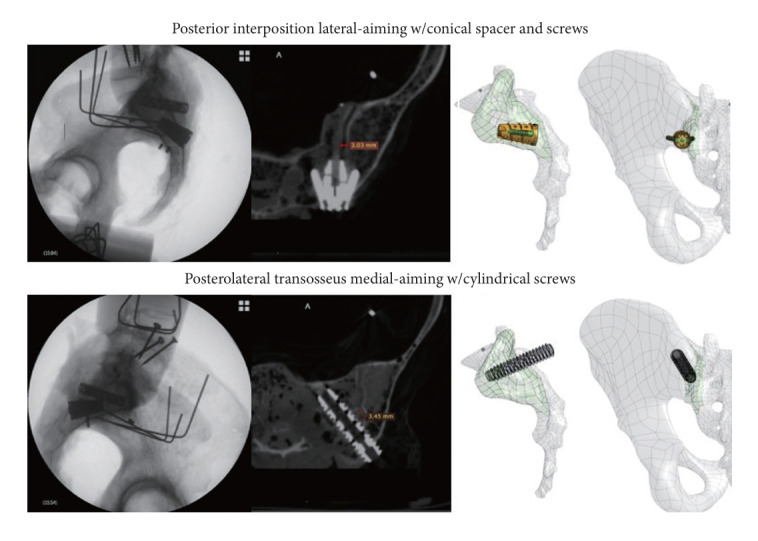

Objective: Our study aimed to compare the posterior interposition technique against the posterolateral transosseous technique in the same cadaver specimens.

Methods: Computer and cadaver models of 2 fixation techniques were developed. The computer model was constructed to analyze bone volume removed during implant placement and the bony surface area available for fusion. The cadaver model included quasi-static multidirectional bending flexibility and dynamic fatigue loading. Relative motions between the sacrum and ilium were measured intact, after joint destabilization, after fixation with direct-posterior and posterolateral techniques, and after 18,500 cycles of fatigue loading. Relative positions between each implant and the sacrum and ilium were measured after fixation and fatigue loading to ascertain the quality of the bone-implant interface. The 2 techniques were randomized to the left and right sacroiliac joints of the same cadavers.

Results: The posterior interposition technique removed less bone volume and facilitated a larger surface area available for bony fusion. Posterior interposition significantly reduced the nutation/counternutation motion of the sacroiliac joint (42% ± 8%) and reduced it more than the posterolateral transosseous technique (14% ± 4%). Upon fatigue loading, the posterior interposition implant maintained the bone-implant interface across all specimens, while the posterolateral transosseous implant migrated or subsided in 20%-50% of specimens.

Conclusion: Posterior interposition fixation of the sacroiliac joint reduces joint motion. The amount of fixation from the posterior technique is superior and more durable than the amount of fixation achieved by the posterolateral technique.